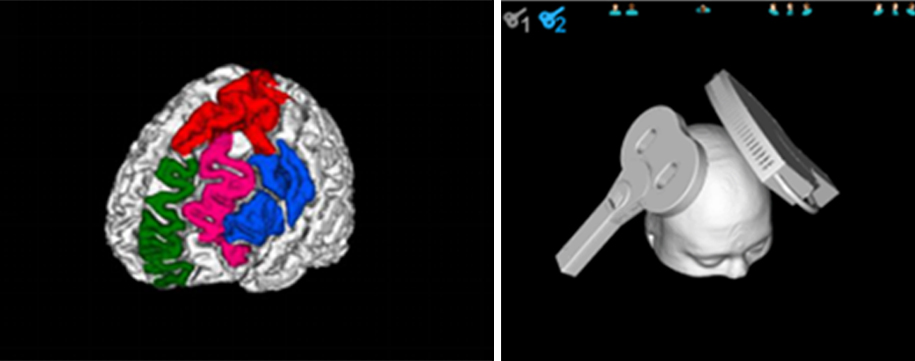

Support Custom Brain Functional Areas

Brain functional area mark: The brain functional area map has been integrated, and can also be customized.

TMS target memory: the system can automatically save the stimulation target and coil position information, and can assist in repositioning when re-treatment.

Stimulation With 2 Coils

Support simulation tracking, navigation and managing paired pulse stimulation with two coils at the same time.